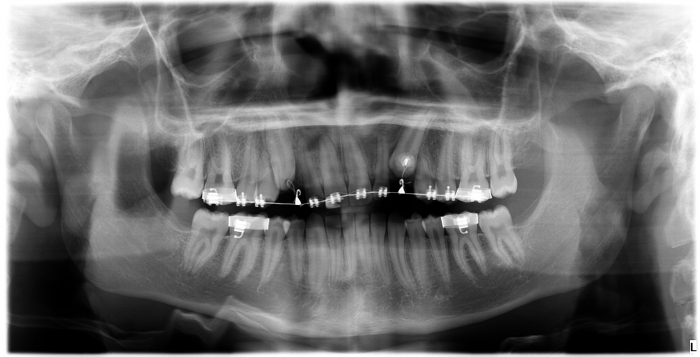

Rx Panorâmico - Caninos inclusos e intra-ósseos - Clínica Cliniface

Rx Panorâmico - Caninos inclusos e intra-ósseos